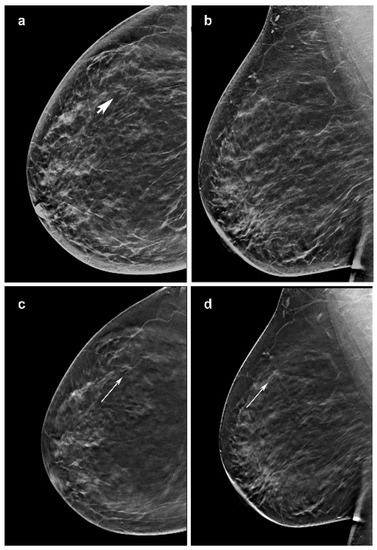

Figure 2.

Invasive lobular carcinoma presenting as a mass in a 57-year-woman, diagnosed at screening. (c,d) Craniocaudal and mediolateral oblique images of the right breast from slices of the DBT portion of the screening study demonstrate a poorly defined 7-mm mass in the outer superior quadrant (arrow). (a) It is less defined in the craniocaudal synthesized mammography (arrow head) and not visible in the mediolateral oblique synthetized mammography oblique image (b).

Other investigations reported that ILC is commonly presented as a mass on mammography. Of note, in our series 10/50 opacities were not recognized by at least one reader at synt2D but were visualized by all the readers at DBT. Two out of ten tumors with small diameter were identified in fatty breast only at DBT by all the readers (Figure 2). This could be explained by the better capabilities of DBT than synt2D in the evaluation of spiculated or ill-defined masses (Figure 3). Our results confirmed that calcifications with or without opacity due to their high density are easy to detect on both synt2D and DBT.